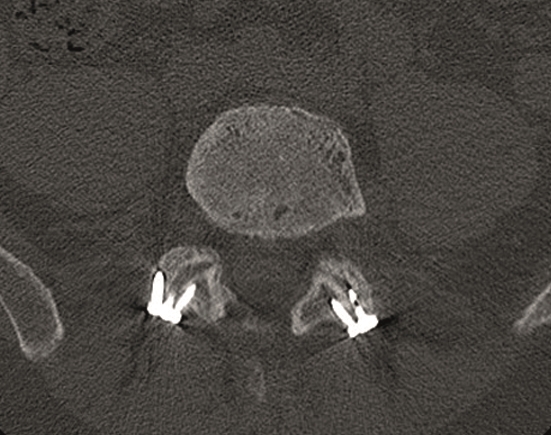

Multilevel facet pathology is shown in Fig 6. Intraoperative and postoperative images are shown (Fig 7-9).

A 40-year-old man 5 years after ALIF L4-L5 using SynFix with axial low back pain. The CT scan shows locked pseudarthrosis (Fig 17). Nonoperative treatment failed. The treatment option was bilateral Facet Wedge at L4-L5.

A less invasive approach was used with Insight Retractor using the bilateral Facet Wedge. No bone graft. X-ray follow-up after 3 months and CT assessment after 6 months (Fig 18-19).